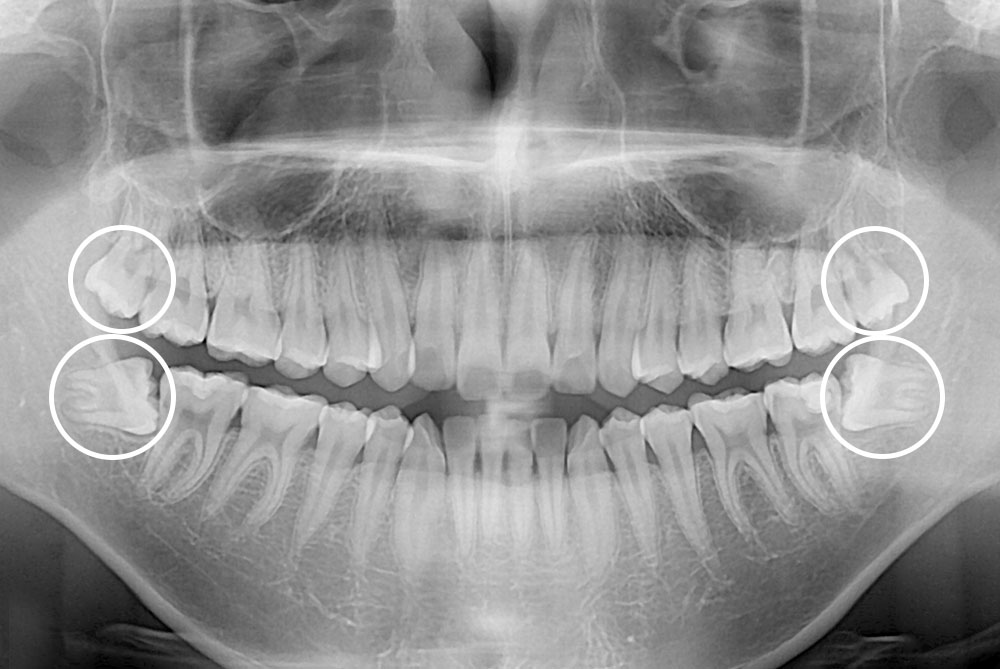

[사랑니] 매복 사랑니 발치

치료후 : 2022-04-12